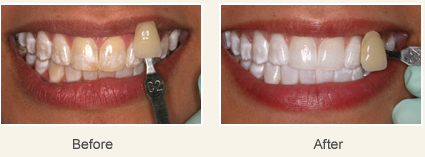

Dental fluorosis is cosmetically treatable. Different treatment options include: tooth bleaching, microabrasion, and conservative composite restorations or porcelain veneers are generally used treatments. Generally speaking, microabrasion and bleaching are utilized for superficial staining, while the conservative restorations are utilized for more unaesthetic situations such as severe fluorosis.

Micro abrasion and Tooth bleaching:

Conservative restorations and porcelain veneers:

Patient with moderate fluorosis. Front six teeth were treated with cosmetic veneers to cover fluoride staining.